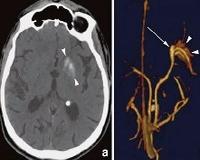

• КТ головного мозга. На компьютерной томографии в первые часы выявляются косвенные признаки патологии: повышенная плотность артериальных стенок, нарушение дифференциации белого и серого вещества, уплощение извилин коры больших полушарий. Зона ишемии становится отчетливо видимой через 10-14 часов после начала заболевания.

• Исследование сосудов головного мозга. Дуплексное сканирование (УЗИ) позволяет оценить состояние церебральной гемодинамики и определить степень закупорки средней мозговой артерии, применяется селективная церебральная ангиография. При необходимости проводится МР-ангиография.